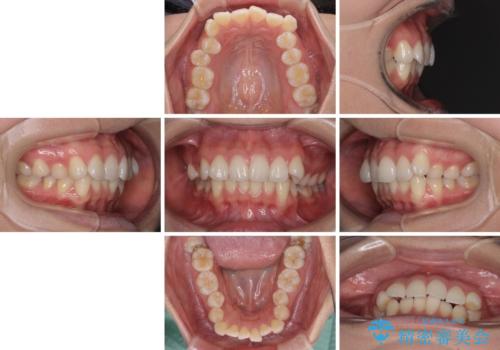

- 前歯のデコボコを治したいとのことで来院された患者様です。

上下顎ともに歯列全体の後方移動とIPR(歯と歯の間を削る)によってデコボコが解消するように設計し、インビザラインにより治療を行うこととしました。